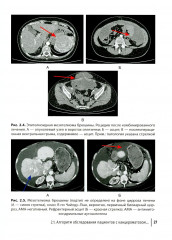

💳 Оплатить за товар можно при получении 🇰🇿 Есть бесплатная доставка по Казахстану 🎁 Копите бонусы с каждой покупки В руководстве представлена информация о перитонеальном канцероматозе, источником которого могут быть разные опухоли: псевдомиксома брюшины, мезотелиома, рак яичников. Отдельные главы посвящены методике циторедуктивных операций, лечебной тактике при продолженном росте псевдомиксомы, возможности сохранения фертильности при канцероматозе и др. Структура книги позволяет рассмотреть частные вопросы, касающиеся индивидуальных особенностей опухолей, и отдельно общие подходы к лечению, которые используются вне нозологического принципа и являются, по сути, унифицированными (например, рентгенологическая диагностика, хирургическая техника, ведение пациентов в послеоперационном периоде). Издание предназначено хирургам, онкологам, химиотерапевтам, акушерам-гинекологам, колопроктологам, рентгенологам. |